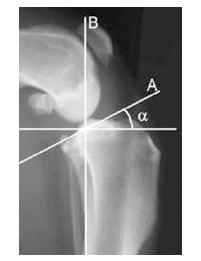

Wenn der Hund sein Bein belastet (A), entsteht im Knie eine Kraft noch vorne (B). Diese Kraft B muss neutralisiert werden, damit das Knie bei Belastung stabil ist. Dafür wird mit einer speziellen Säge der obere Teil des Unterschenkels ausgesägt und mit einer Platte fixiert.

α ist der Neigungswinkel der Gelenks- fläche (A) zur Längsachse des Knochens (B) -